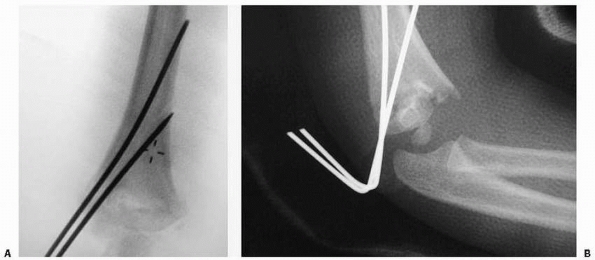

flexion (usually about 45 to 70 degrees). If pinning is chosen, two

alignment (Figs. 14-22 and 14-23), although three pins can be used for added stability.182

![]() |

FIGURE 14-22

FIGURE 14-23

Intraoperative fluoroscopy of two lateral entry pins placed for a type II fracture. (Reproduced with permission from Children’s Orthopaedic Center, Los Angeles, CA.) |